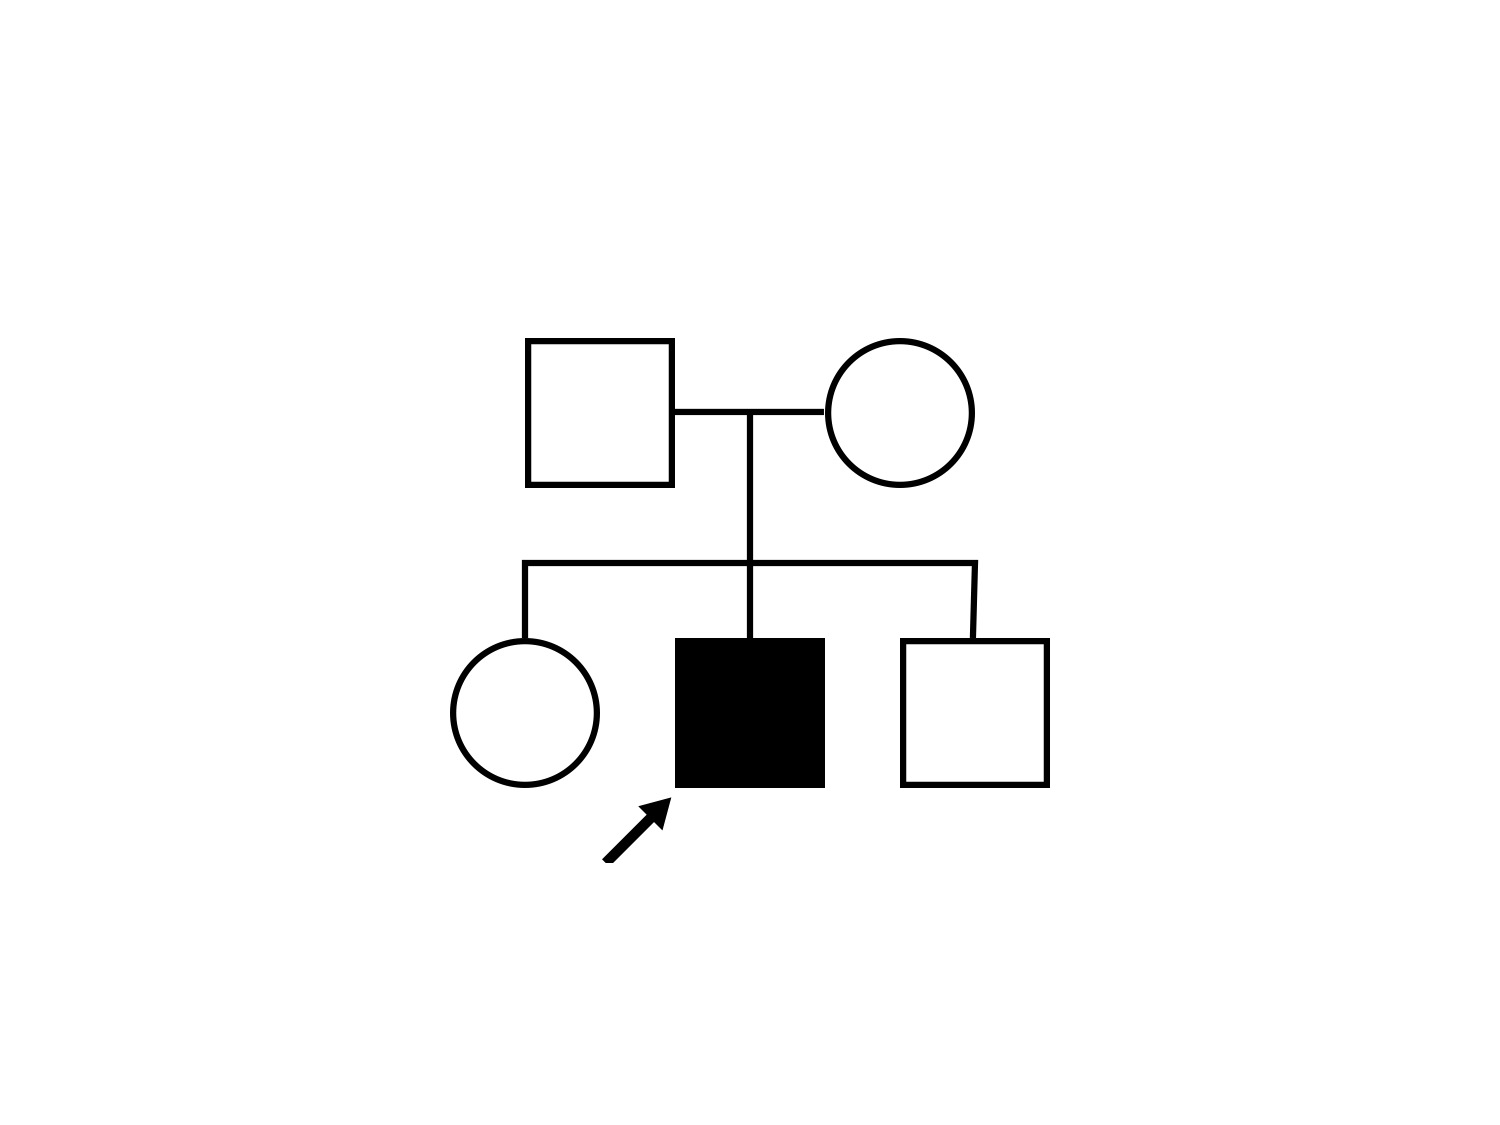

| Disease | Gene | Allele 1 variant(s) | Allele 2 variant(s) | Inheritance mode |

|---|---|---|---|---|

| XL Retinoschisis | RS1 | Pro192His CCC>CAC | XL |